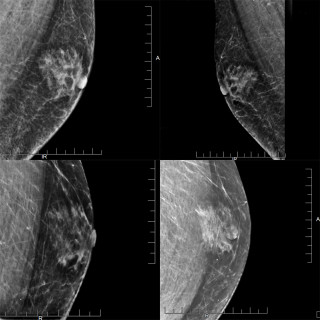

Bildet viser leukemiske hudinfiltrasjoner hos en mann i 50-årene diagnostisert med akutt myelogen leukemi. Pasienten ble overført fra lokalsykehus til hematologisk avdeling ved universitetssykehus, der han ble innlagt med spørsmål om alvorlig infeksjon. Han hadde da 14 dagers sykehistorie med tiltakende luftveissymptomer, økende dyspné og fallerende allmenntilstand. De siste fire dagene var det også tilkommet flere flekkvise, nodulære hudlesjoner, mest uttalt på hals, bryst og overekstremiteter. Blodprøver ved ankomst universitetssykehuset viste hemoglobin 8,1 g/dL (referanseområde 13,4–17,0)...